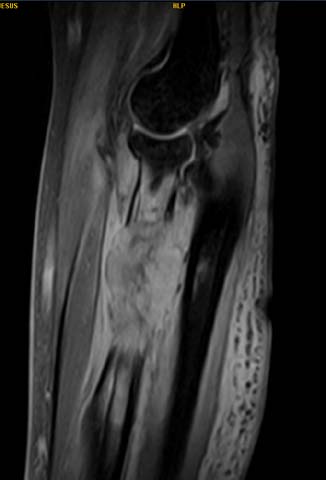

The extra-focal technique was performed under general or local anaesthesia, then close reduction was achieved by traction and counter traction and then with proper flexion the reduction was achieved in all cases under fluoroscopy guidance. After this, we make the first stab wound through first and second extensor compartment and after mobilization of underlying tendons and soft tissue we inserted the first K wire through radial styloid and cross the fracture site and go through the opposite cortex about 1-2 mm. The second K wire was passed from the lunate fossa cross the fracture site piercing the opposite cortex for about 1-2mm and the third wire was again passed through the radial styloid cross the fracture site and go through the opposite cortex about 1-2 mm and distal to the piercing of the cortex done by the previous k wire inserted from the styloid. Preoperative, postoperative and 6 month follow up images of the 2 techniques is given in Figure 1.